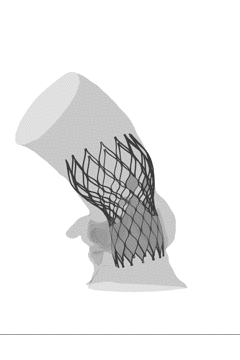

L26号瓣膜高位植入后主动脉受压情况

L26号瓣膜标准位植入后主动脉受压情况

FEops量化评估瓣周漏

根据FEops评估报告得知,L26号瓣膜在高位和标准位释放之后,分别会产生4.4m/s和5.7m/s的瓣周漏,但均小于FEops评估瓣周漏无至轻度和中至重度的临界值16ml/s,所以两种释放位置都可以考虑。

L26号瓣膜高位植入后的瓣周漏

L26号瓣膜标准位植入后的瓣周漏

FEops评估瓣膜释放稳定性

根据FEops评估报告得知,L26瓣膜在高位释放与标准位释放之后,最终稳定位置与初始位置差异不大,评估瓣膜在这两个位置释放比较稳定,发生瓣膜移位的风险比较小。

L26号高位植入后的稳定形态

L26号标准位植入后的稳定形态